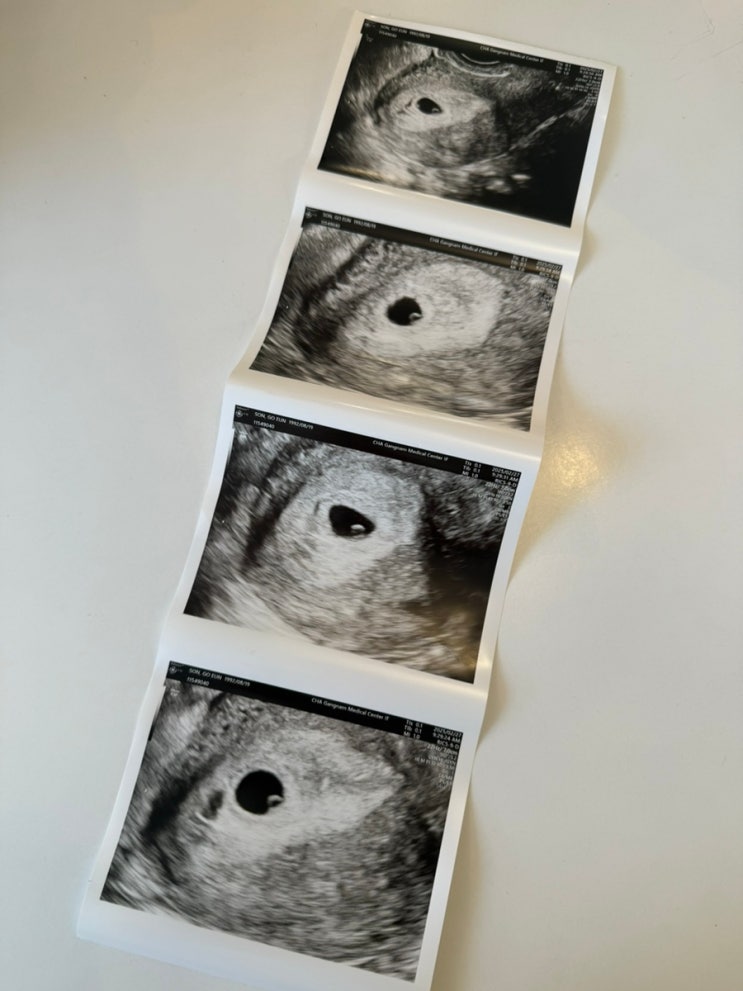

임신 6-7주 차, 심장소리, 갈색냉, 부모님 임밍아웃 이벤트

아기집과 난황을 보는 것이 보통 5주 차~ 좀 늦으면 6주 차이고, 그다음 6~7주 차 정도에는 아기 심장소리...

내돈내산 일상유희 초음파 앨범 다이어리

초음파 사진을 어떻게 보관할까,,, 그냥 기존에 쓰던 종이 다이어리에 붙일까? 했는데 초음파 앨범 다이어...